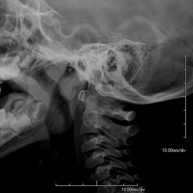

Tècnica que usa els raigs X a través de la qual s'obtenen imatges del càvum per al seu estudi. Indicacions: dificultat respiratòria, angines de repetició en lactants i nens - RX Columna cervical

Tècnica que usa els raigs X a través de la qual s'obtenen imatges de la columna cervical per al seu estudi. Indicacions: traumatisme, contractura cervical, dolor articular. - RX Ossos propis nasals

- RX Columna cervical

Tècnica que usa els raigs X a través de la qual s'obtenen imatges de la columna cervical per al seu estudi. Indicacions: traumatisme, dolor cervical. - RX Columna dorsal